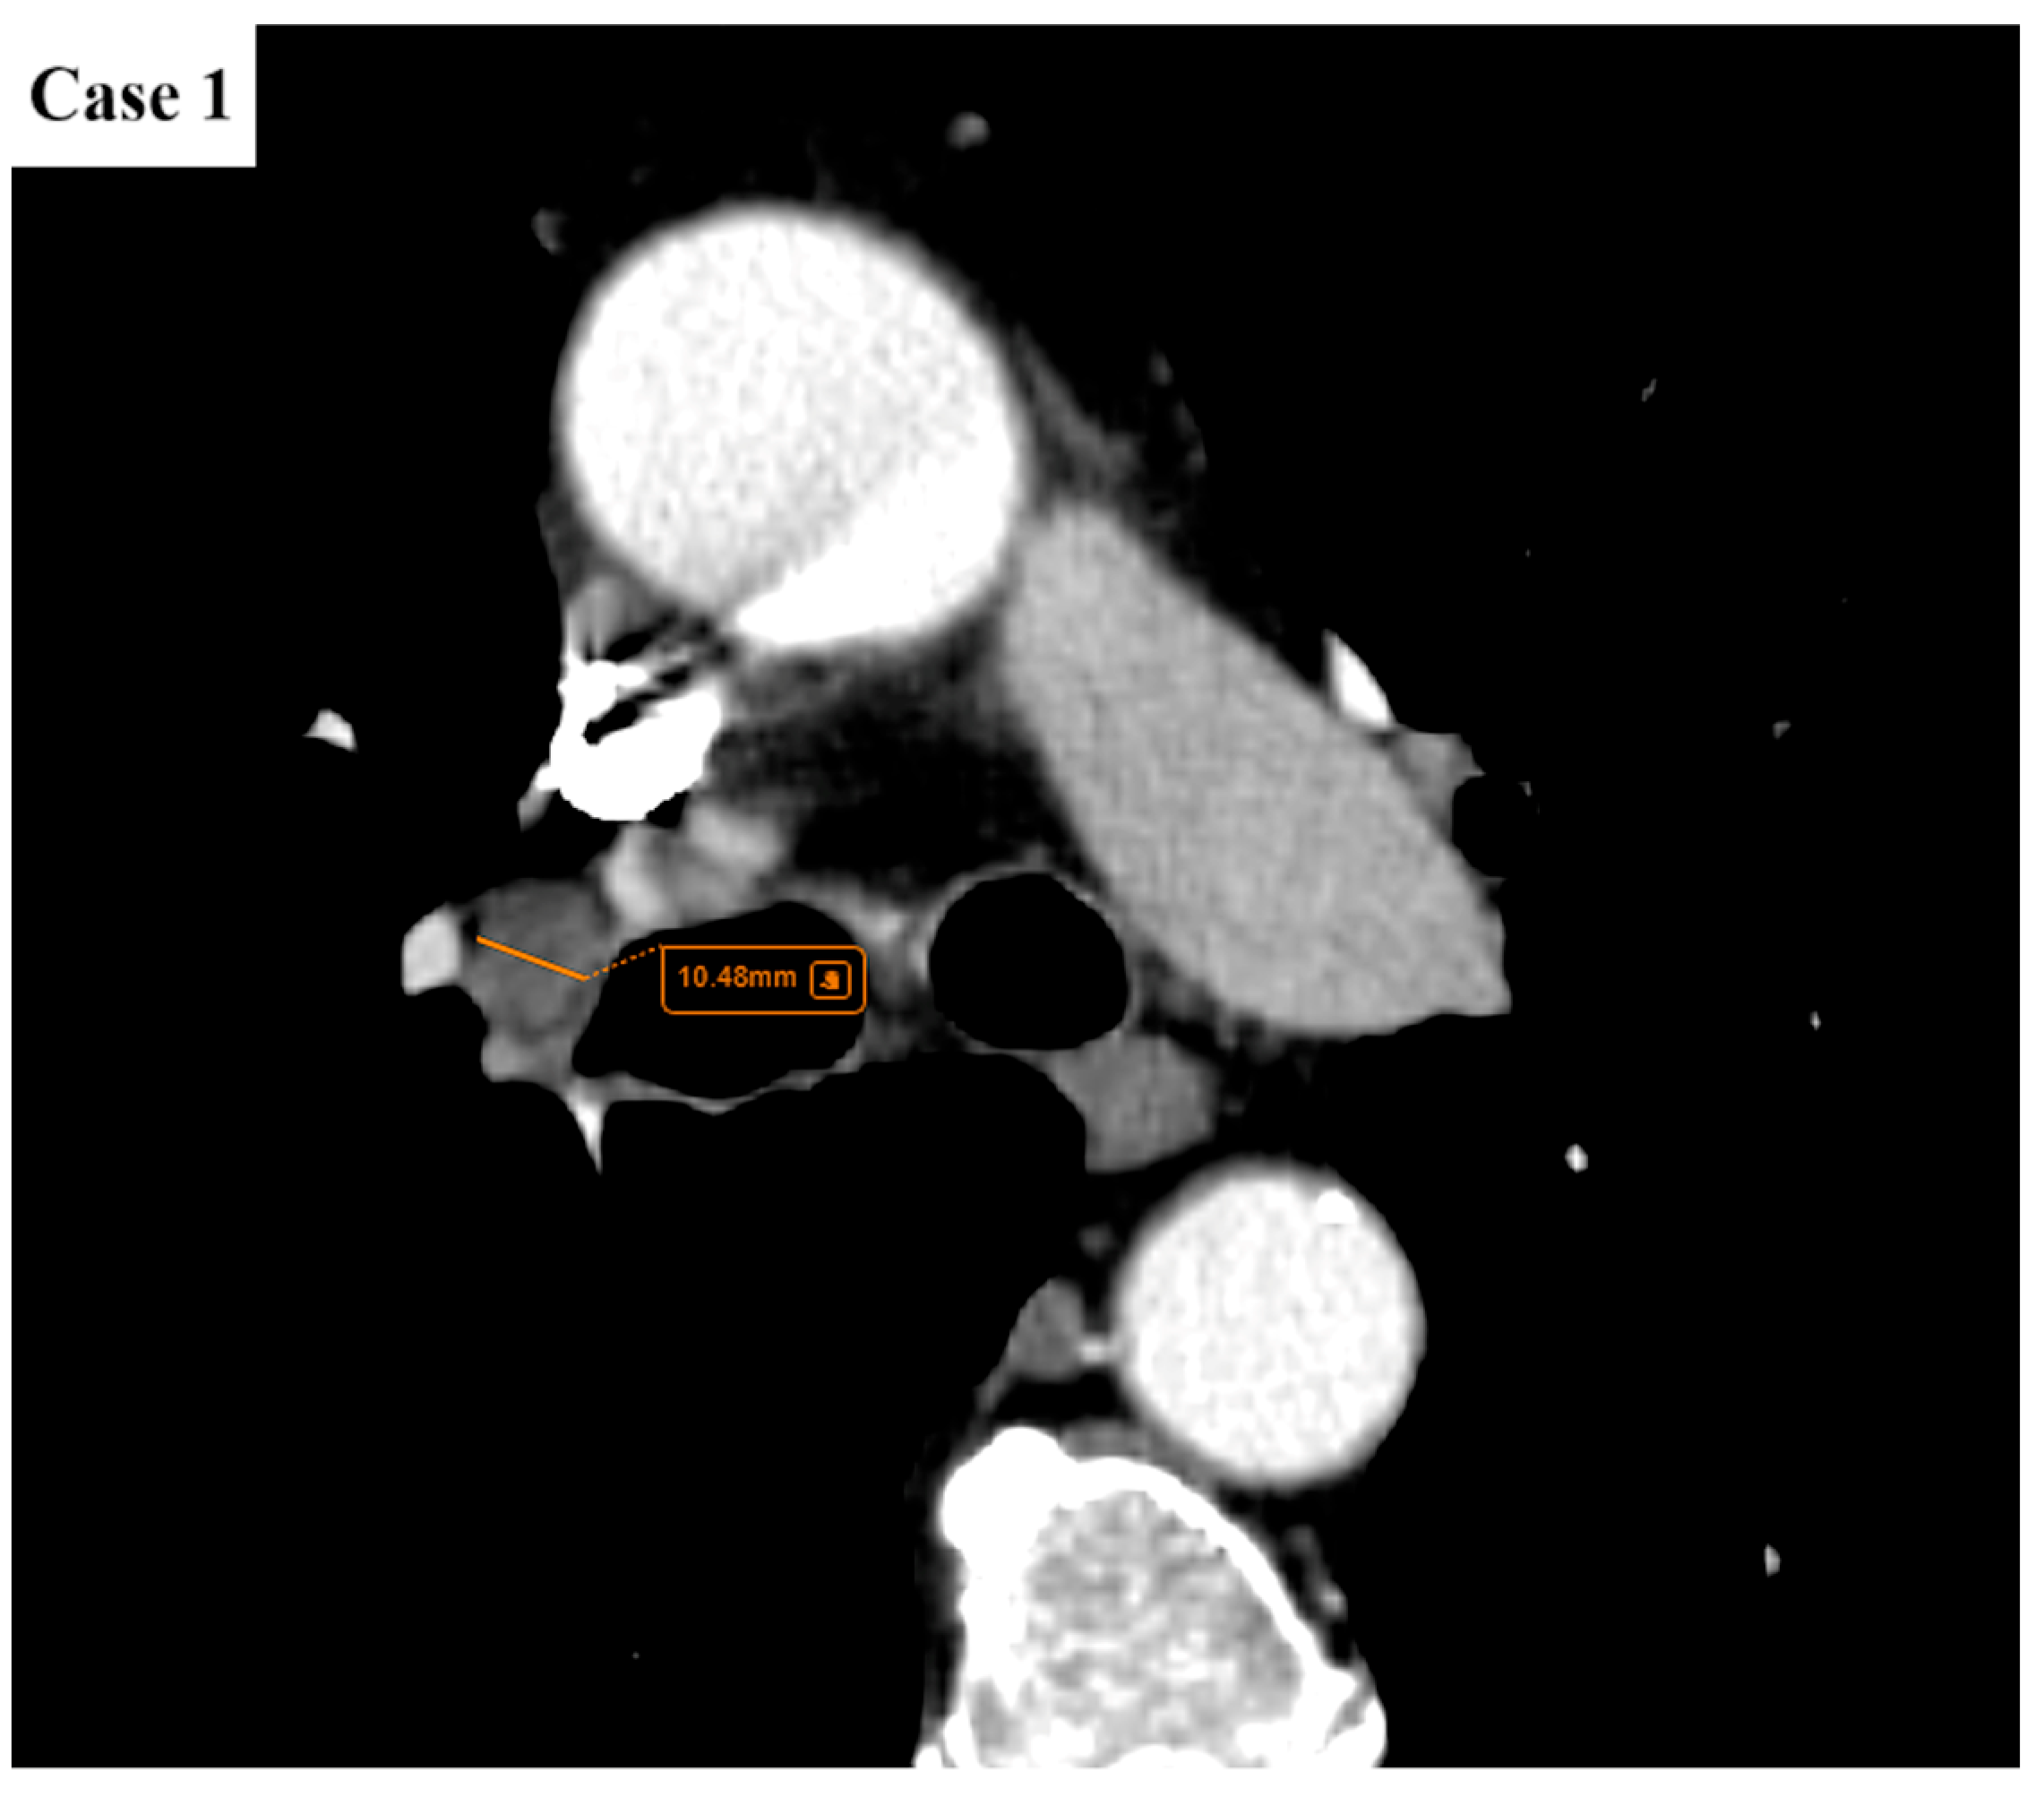

- Argentieri, G.; Valsecchi, C.; Petrella, F.; Jungblut, L.; Frauenfelder, T.; Del Grande, F.; Rizzo, S. Implementation of the 9th TNM for Lung Cancer: Practical Insights for Radiologists. Eur. Radiol. 2025, 35, 4395–4402. [Google Scholar] [CrossRef] [PubMed]

- Erasmus, L.T.; Strange, C.D.; Ahuja, J.; Agrawal, R.; Shroff, G.S.; Marom, E.M.; Truong, M.T. Imaging of Lung Cancer Staging: TNM 9 Updates. Semin. Ultrasound CT MRI 2024, 45, 410–419. [Google Scholar] [CrossRef]